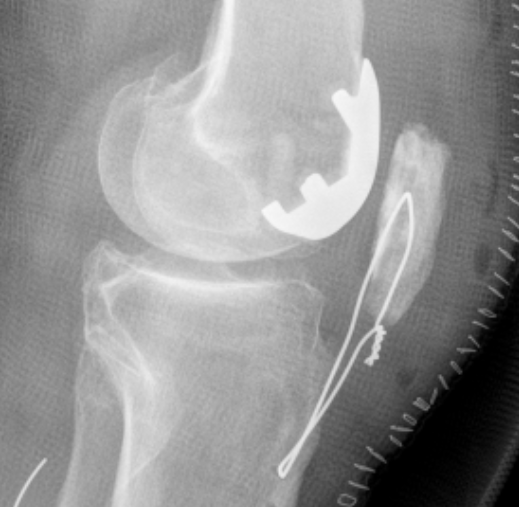

Patellofemoral joint replacement

Patella maltracking / malalignment

Tibiofemoral arthritis / medial or lateral joint pain / instability